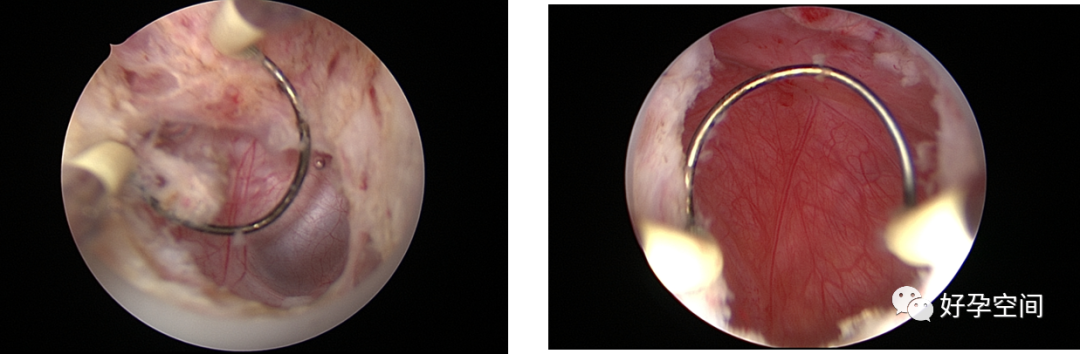

6、宫腔镜输卵管开口电凝封堵绝育、输卵管开口置入弹簧圈封堵绝育、胚胎移植前阻断输卵管积水返流入宫腔。

试管助孕前双侧输卵管积水,腹腔镜及开腹手术失败,宫腔镜电针电凝封堵输卵管开口

既往试管助孕前输卵管开口植入弹簧圈,再次移植前宫腔镜检查,弹簧圈包埋组织内,不见痕迹

7、最近有专家在研究宫腔镜下的缝合技术。

宫腔镜下缝合固定曼月乐环